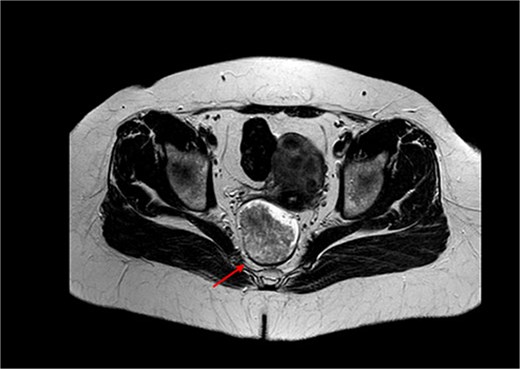

Pelvic magnetic resonance imaging (MRI) revealed a solid, stenosing lesion located 27 mm from the anal verge, extending from the 7 o’clock to 11 o’clock position, infiltrating the muscular layer but without mesorectal fascia invasion. The lesion measured 73 mm longitudinally and 51 mm in both anteroposterior and transverse diameters, located in the mid-to-low rectum, staged as T3N0M0 (Figs 1 and 2).

MRI of the pelvis in axial view demonstrating a solid, stenosing lesion located 27 mm from the anal verge. The lesion infiltrates the muscular layer between the 7 and 11 o’clock positions and causes changes in the intensity of the mesorectal fat without fascia involvement.